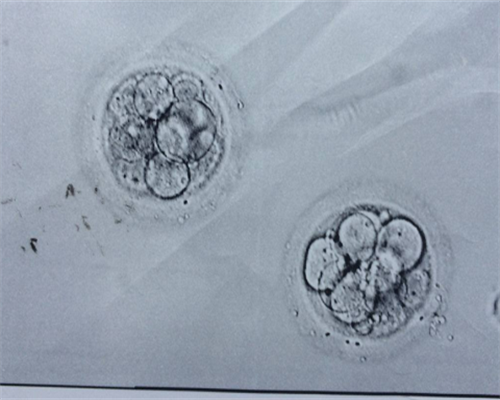

1999年,安徽医科大学第一附属医院生殖中心开始运营,妊娠成功率稳定在40%-50%,达到国内先进水平。可进行常规体外受精-胚胎移植、单精子卵母细胞注射、附睾取精微授精试管婴儿、冻融胚胎试管婴儿、人工授精技术、选择性多胎妊娠减胎、冷冻精子试管婴儿、未成熟卵母细胞体外成熟培养技术(IVM)等。